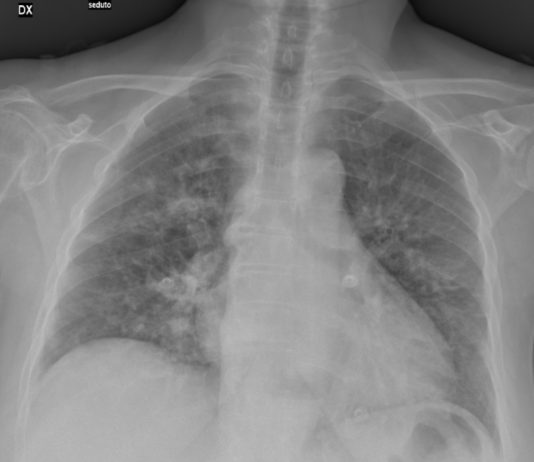

49-year-old male

patient admitted to the ED with fever (39°C) and...